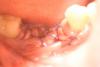

Pavel Y. Опубликовано 19 июля, 2013 Поделиться Опубликовано 19 июля, 2013 Не пойму, что в лунке винта? Перед ушиванием.... Ссылка на комментарий

OMFS Опубликовано 19 июля, 2013 Автор Поделиться Опубликовано 19 июля, 2013 Не пойму, что в лунке винта? Перед ушиванием....PRF Ссылка на комментарий